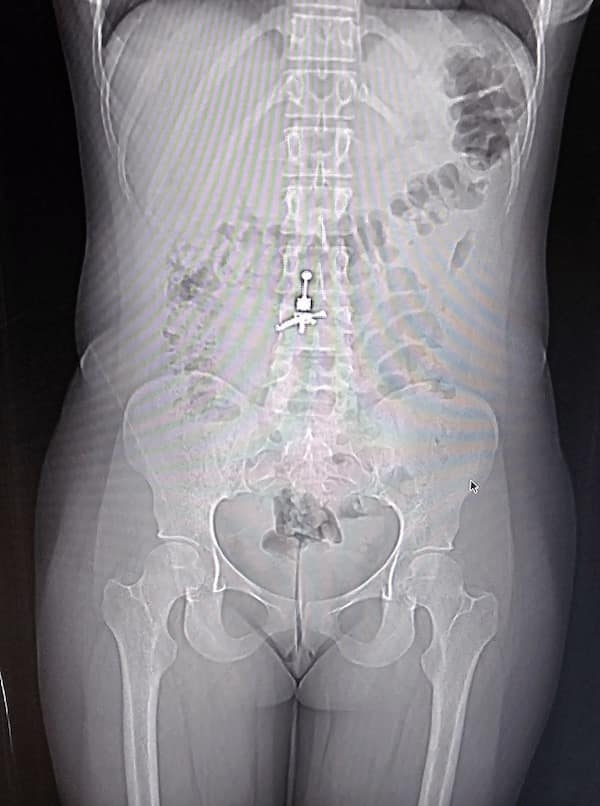

This collection showcases 31 bizarre x-ray images that defy logic and anatomy textbooks alike. Each photo reveals unexpected objects making cameo appearances inside the human body, turning medical imaging into a gallery of the absurd. From common household items inexplicably found in unusual places to anomalies that would leave even seasoned doctors scratching their heads, these images offer a perplexing glimpse into the more “creative” side of medical emergencies. They highlight the intersection of curiosity, misadventure, and perhaps a dash of poor decision-making, all captured through the lens of radiology.